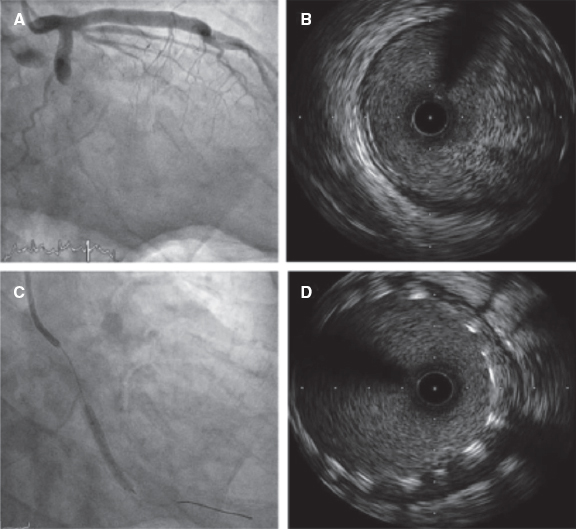

Predilatation occurred in 32 lesions (51.6%) and postdilatation in 37 (59.7%). The criterion used for postdilatation was angiography guided visual underexpansion. Intravascular ultrasound was performed in 15 patients (30%) before the implant. It was also used in 2 patients to optimize the percutaneous coronary intervention given the persistent stent underexpansion seen on the angiography. In both cases the minimum lumen area was > 5.5 mm2 with stent expansion > 80% and lack of incomplete apposition (defined as a strut separation of > 0.4 mm axial and 1 mm longitudinal) (figure 2). The optical coherence tomography was performed in a patient with ST-segment elevation acute coronary syndrome before and after the implant. It revealed a high thrombotic load with lack of immediate stent malapposition.

Figure 2. A: acute thrombotic occlusion in left circumflex artery with Thrombolysis in Myocardial Infarction flow grade 0. B: the intravascular ultrasound shows a great deal of thrombus in the lesions despite thrombus aspiration. C: implantation of 2 3.5-4.5 mm × 27 mm Xposition S overlapping stents. D: the intravascular ultrasound performed after stent implantation confirms the good angiographic results and lack of stent malapposition.